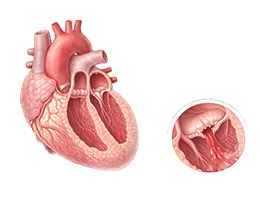

심근경색 (Myocardial Infarction)

협심증 (Angina Pectoris)

심근병증 (Cardiomyopathy)

심장판막질환 (Valvular Heart Disease)

심부전 (Heart Failure)

비대성심근병증 (Hypertrophic Cardiomyopathy)

확장성심근병증 (Dilated Cardiomyopathy)

울혈성심부전 (Congestive Heart Failure)

심근염 (Myocarditis)

심막염 (Pericarditis)

심내막염 (Endocarditis)

심정지 (Cardiac Arrest)

돌연심장사 (Sudden Cardiac Death)

심방세동 (Atrial Fibrillation)

심실빈맥 (Ventricular Tachycardia)

심실세동 (Ventricular Fibrillation)

서맥 (Bradycardia)

심장판막질환 (Heart Valve Disease)

폐동맥고혈압 (Pulmonary Hypertension)

심장병성쇼크 (Cardiogenic Shock)

심장막압전 (Cardiac Tamponade)

확장형심근병증 (Dilated cardiomyopathy)

비후성심근병증 (Hypertrophic cardiomyopathy)

제한성심근병증 (Restrictive cardiomyopathy)

감염성심내막염 (Infective endocarditis)